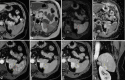

Figure 3. Dynamic MRI examination

On non-contrast fat-suppressed T1-weighted axial imaging (a) and T2-weighted axial imaging (b), the lesion (black arrows) demonstrates iso-hypointense signal characteristics. On diffusion-weighted imaging (c) and ADC imaging (d), no significant diffusion restriction is observed. In T2-weighted imaging (b) and diffusion-weighted imaging (c), a centrally located hypointense scar (red asterisks) is noted. Following the administration of contrast material, on arterial T1-weighted imaging (e), the lesion (yellow arrows) demonstrates weak peripheral enhancement (red asterisks) compared to the splenic parenchyma. On post-contrast portal venous phase (f), delayed venous phase axial (g), and coronal (h) images, the lesion exhibits progressive centripetal enhancement (yellow arrows). In delayed venous phase images (g, h), hypointense signal characteristics consistent with a central scar are observed (black arrows).